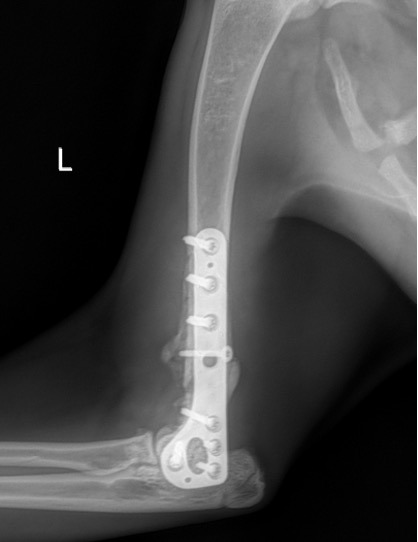

Exemple 3 :

Figure 9 : Pré-Op

Figure 10 : Opération

Figure 11 : Post-Op Immédiat

L’avènement récent des plaques anatomiques constitue une nouvelle option dans le traitement de ces fractures : dans l’exemple 3 (chat Ragdoll), une plaque anatomique médiale de 2 mm acceptant des vis de 1,6 et 2 mm a été utilisée seule avec succès.